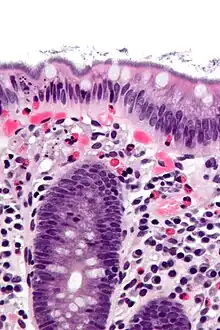

| Histopathology of intestinal spirochetosis, showing basophilic, fringe-like, end-on-end attachment of filamentous densely packed spirochetes on the surface epithelium of the intestinal mucosa.[1] H&E stain. | |